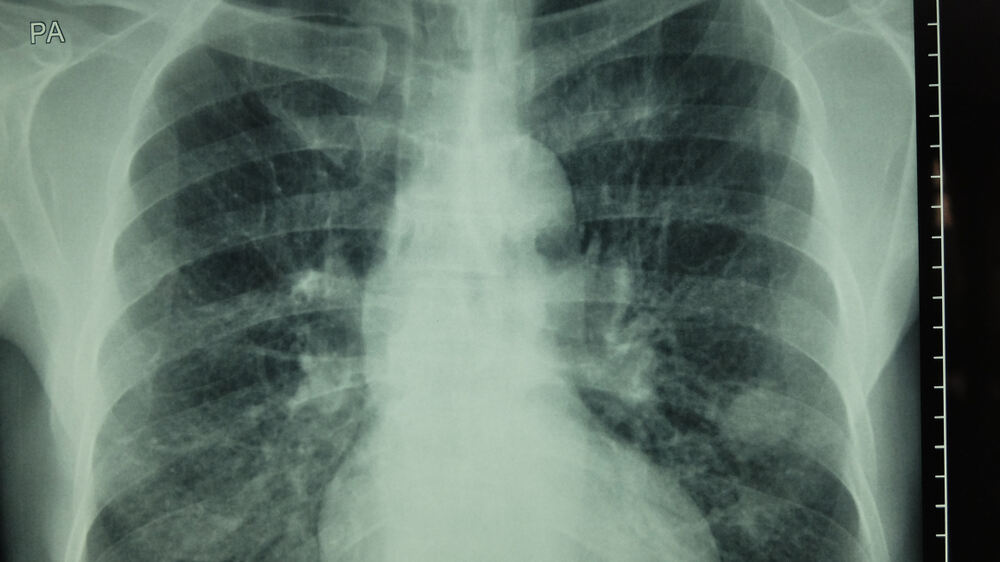

For those at high risk of lung cancer, Riverside is proud to offer a free lung cancer screening program with low-dose CT, a groundbreaking new tool to catch the disease earlier than ever. The scan provides incredibly detailed pictures to help our physicians detect even the smallest of tumors. It’s safe, painless and has proven to reduce the risk of lung cancer death by up to 20%.

Riverside Cancer Team members reviewing imaging results